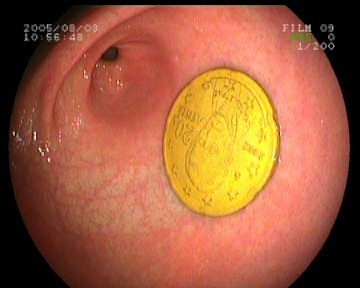

Gastroskopie - verschluckte 20-Cent-Münze im Magen